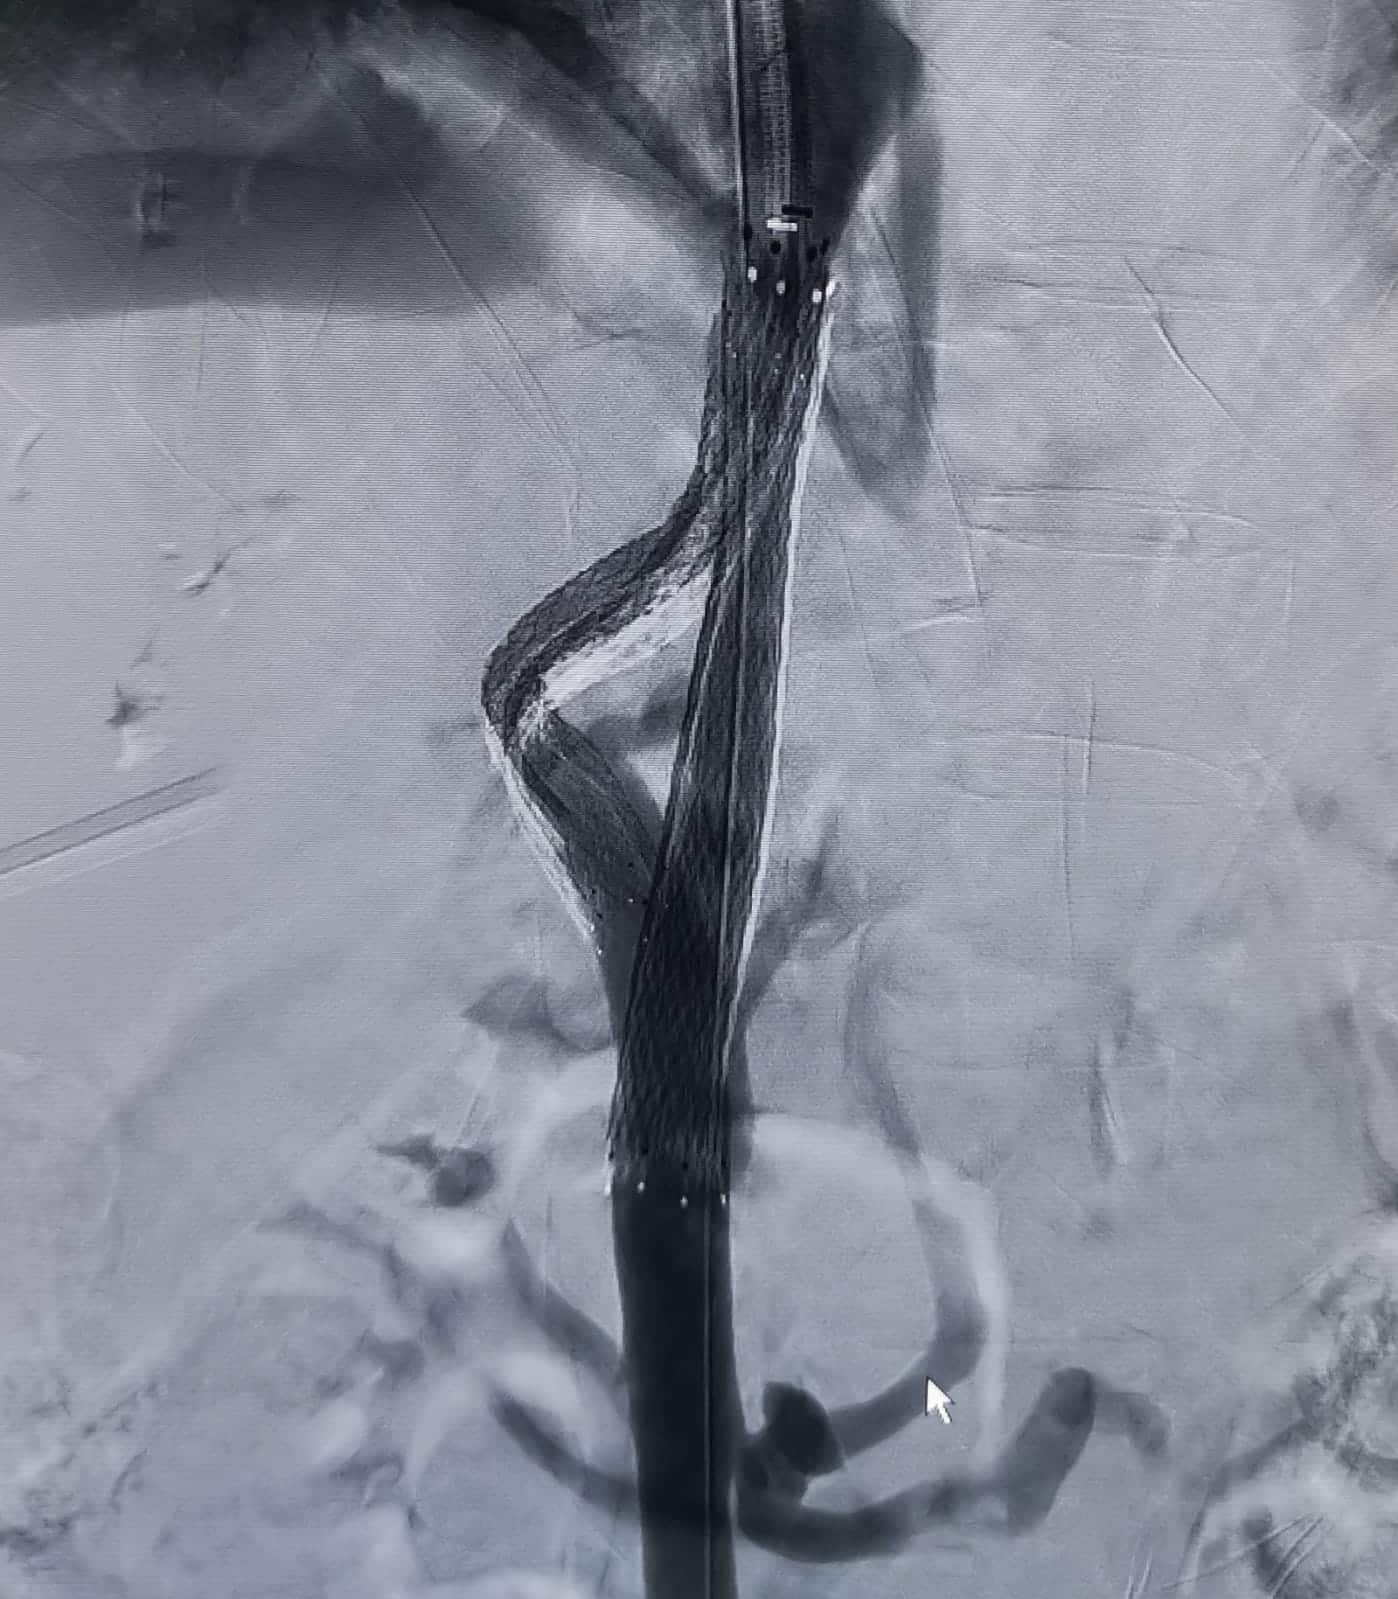

أجرى فريق طبي متخصص في مستشفى الملك المؤسس عبد الله الجامعي اليوم الخميس، عملية قسطرة معقدة ونوعية داخل الكبد لسيدة من دولة عربية شقيقة في الأربعين من العمر تكللت بالنجاح لعلاج الاستسقاء البطني ودوالي المريء الناتجة عن انسداد الأوردة وتشمع الكبد.

وقال رئيس الفريق الطبي المشرف على العملية؛ استشاري الأشعة التداخلية الدكتور مأمون العمري إن السيدة كانت تعاني من انسداد تام ومزمن في أوردة الكبد، أي ما يعرف بمتلازمة (بد كياري ) مصاحبة لإنسداد كامل في الوريد الأجوف السفلي، ما تسبب لها بتشمع الكبد نتج عنه تجمع كبير للسوائل داخل البطن ونزيف متكرر داخل المريء ودوالي على جدار البطن.

وأشار إلى أن العملية جرت من خلال ثلاثة قسطرات متزامنة وتركيب شبكات خاصة داخل الكبد والوريد الأجوف السفلي.